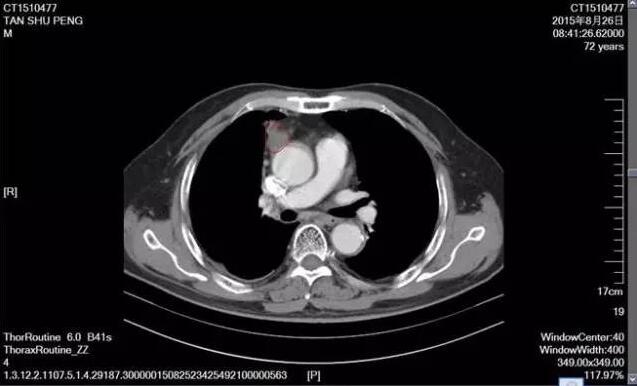

下面這張是2015年8月份復查的CT片,腫塊開始縮小,放療完畢患者一般狀況可,期間曾出現(xiàn)過輕度放射性食道炎,經(jīng)對癥處理,患者基本恢復,無特殊不適。